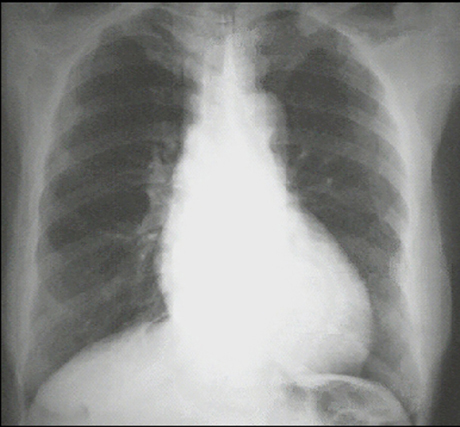

PA and Lateral

Click on the xrays to enlarge them.

Choose the best interpretation of the chest X rays:

Left ventricular enlargement + dilated aorta